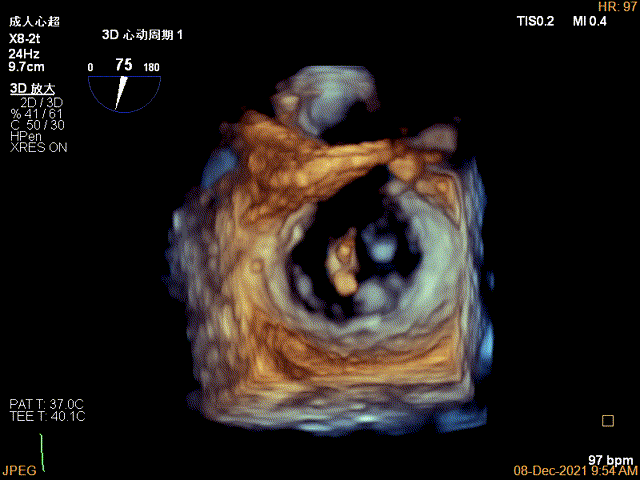

患者麻醉方式为全麻,建立静脉通路后,穿刺右侧股静脉,预埋ProGlide缝合器,食道超声指导下房间隔穿刺成功,将Superstiff导丝送至左房,应用18F鞘管扩张穿刺部位,沿导丝将导引导管送入左房,应脉MSG0101操作系统调整后顺利到达二尖瓣目标位置,在食道超声辅助下,将成形夹(MCD0100)精确定位后,成功夹合二尖瓣A2-P2区,超声显示少量残余分流,整体反流量改善至少2级以上,后多切面证实夹合组织充分,肺静脉多普勒波形由反向恢复正常,手术顺利结束,安返普通病房。

术中及术后即刻超声评估

3D视图菲薄的卵圆窝,穿刺点位近似于3点位

3D视图下大鞘位置及长度测量

3D视图下调整夹子位置及Rotate

X-plane:下夹子尝试先捕获2区瓣叶

夹子关闭过程中,Color提示2区反流逐渐减少,残余反流位于夹子外侧

3D-VIEW验证结果

3D-Color-view验证残余分流位于外侧